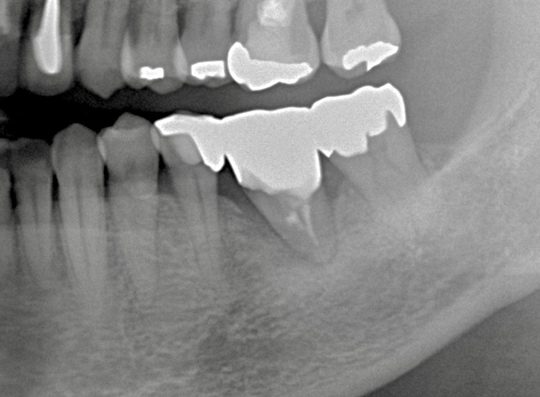

術後3年経過

骨もしっかり増生してよく機能しています。